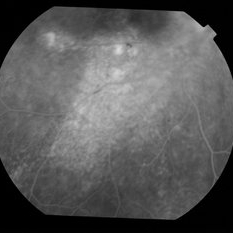

Enough PRP? (Proliferative Diabetic Retinopathy With Extreme PRP and Widespread Atrophy)

Fluorescein angiogram from a 71-year-old woman who underwent numerous sessions of pan retinal laser photocoagulation for proliferative diabetic retinopathy in the remote past. Note the widespread severe secondary atrophy, with only the central macular RPE remaining. Note the choroidal vessels through the diffuse window defect in the peripheral macula and near periphery.

Condition/keywords: laser injury, laser photocoagulation, proliferative diabetic retinopathy (PDR)